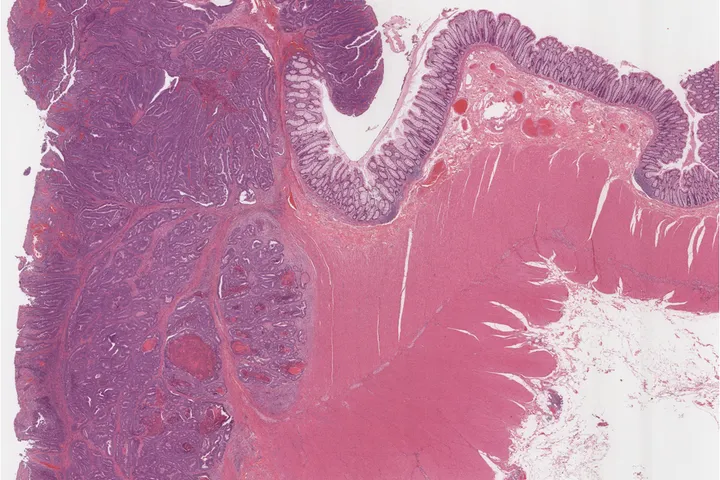

Colon cancer